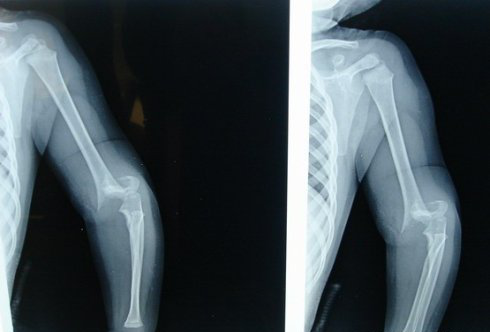

受伤后摄片